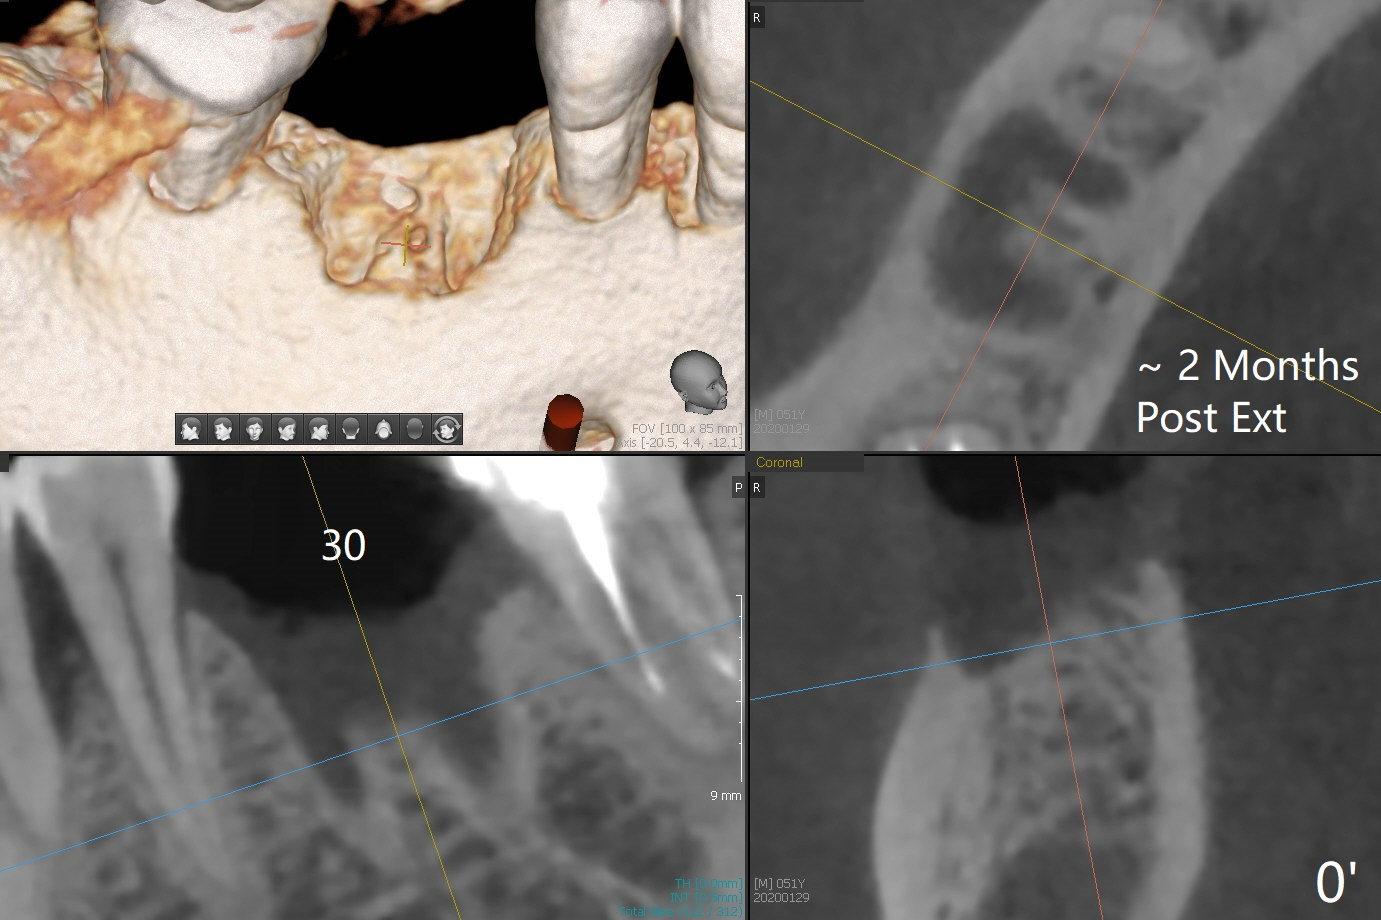

The sockets of #30 (M) of a smoker (M) are apparently not healing ~ 2 months post extraction (Fig.0, 0'). The ridge looks wide 3 months post extraction without bone graft in other office before (Fig.1) and after (Fig.2) flap surgery. The socket appears to have healed perfectly consi-dering buccal defect (M) revealed by CT ~ 1 month earlier. When a 5x10 mm implant is placed with guide and high torque (in spite of overprep), granu-lation tissue is found mesio-buccal (MB, Fig.2 *). After curettage, bone graft is placed around the implant, especially MB (Fig.3 *), followed by PRF. Periodontal dressing dislodged a few days postop because of mastication on the right side (Fig.4), whereas the anterior one (24/26) remains in place. There is a small gap around the implant when it is uncovered (Fig.5 arrowheads). It appears that some of bone graft gets lost from the incision (smoker). A 6.5x5.5(4) mm cemented abutment is seated and torqued at 30 Ncm before impression (Fig.6). There is no bone loss 11 months post cementation (Fig.7).